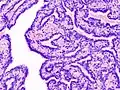

| Histopathology of intraductal papilloma of the breast by excisional biopsy. Immunostaining for p63 protein. | |

Histopathology of intraductal papilloma of the breast by excisional biopsy. Hematoxylin and eosin stain. -